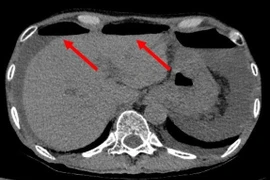

Bệnh viện TWQĐ 108 vừa tiếp nhận một bệnh nhân nữ, 73 tuổi, vào viện vì đau bụng, sốt cao. Bác sĩ nghi ngờ thủng tạng rỗng. Kết quả CT là dị vật vỏ thuốc làm thủng tá tràng.

Thủng tạng rỗng do nhiều nguyên nhân như u ruột, dị vật, tai nạn giao thông hoặc biến chứng của loét dạ dày – tá tràng.... Nhiều người nhập viện do thủng tạng rỗng viêm phúc mạc toàn thể nguy hiểm tính mạng.

Thủng tạng rỗng nếu không được chẩn đoán sớm và xử trí kịp thời sẽ biến chứng đe dọa tính mạng bệnh nhân, đây là tình trạng cấp cứu hết sức nguy hiểm vì ổ bụng bị nhiễm khuẩn do phân gây viêm phúc mạc toàn thể.